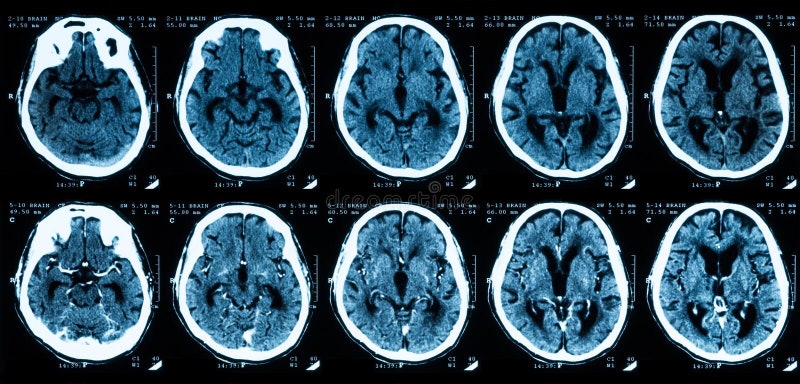

4.3(월) 아빠 뇌경색&눈물 CT 결과 새벽 5시 반쯤 여동생으로부터 긴급 전화가 걸려왔다.”언니! 아빠가 집에서 갑자기 쓰러져서 119를 타고 응급실로 가고 있대” 전화를 끊고 바로 응급실로 향했다.”하나님 아직 아니에요~” 위독한 상황이라지만 내 마음은 왠지 편안했다.아버지는 응급실에서 여러 검사를 받자마자 뇌혈관 조영술을 받고 중환자실에 입원하게 됐다.

* 뇌혈관 조영술법 혈관조영술은 사타구니 근처 허벅지 또는 손목, 팔꿈치 안쪽 피부를 절개한 후 동맥에서 카테터를 넣어 혈관에 조영제를 주입합니다. 그 후 X선 촬영을 하면 뇌혈관을 볼 수 있습니다.혈관의 전체적인 모양이나 혈관이 막힌 정도를 파악할 수 있는 정확한 검사 방법입니다.환자가 뇌졸중을 일으키거나 의심증상을 보일 경우 뇌CT와 뇌VR 촬영검사 결과에 따라 혈관조영술을 시행하기도 합니다.

평소 자주 머리가 아프고 숨쉬기 힘들다고 하셨는데 그게 뇌경색 전조증상인 줄 모르고 두통약만 먹고 있었던 것이다.혈액이 걸쭉해지면서 생긴 혈전이 혈관을 좁히거나 막아서 혈류를 가로막아 매우 멈추고 쓰러진 것이다.

혈전으로 인해 혈관이 막힐 경우 혈액순환이 불가능해지고, 이로 인해 뇌로 들어가는 혈류가 제한될 경우 뇌졸중이 발생할 수도 있다.이외에도 심장으로 들어가는 혈류를 막으면 심장마비, 급성 심근경색 등이 발생할 수 있다.

쓰러지기 전 신체 왼쪽 부분(왼쪽 얼굴 팔 다리)도 마비됐다고 한다. 다행히 골든타임 내 병원으로 이송돼 바로 시술을 받을 수 있었다.신의 은총이라고 밖에 설명할 수 없다.중환자실에 처음 가봤어.누워 있는 아버지보다 맞은편에 있던 아이를 보고 눈물이 날 뻔했다. 머리카락이 없는 걸 보니 암 환자 같았어. 우리 딸보다 한두 살 연상으로 보였는데… 같은 암환우라 너무 마음이 아팠다.폭풍처럼 불어닥친 사건들이 정리되고…

마침 오늘은 12차 항암을 마치고 찍은 CT 결과를 보기로 한 날이었다.다행히 같은 병원이라 아버지 시술이 잘 돼 중환자실에 가서 면회까지 한 뒤 시간을 맞춰 혈액종양내과로 외래를 갔다.CT 결과를 확인한 교수가 다른 곳은 괜찮지만 목에 있는 림프절 의심 증상이 있어 다시 한번 조직검사를 해봐야 할 것 같습니다.만약 암이라면 항암+방사선+조혈모세포 이식을 해야 합니다.”항암+방사선+조혈모세포 이식이요?” 종합선물세트도 아니고… 이건 꿈인가? 현실인가?오늘 하루 있었던 많은 일들을 어떻게 해석해야 할지 막막했다.